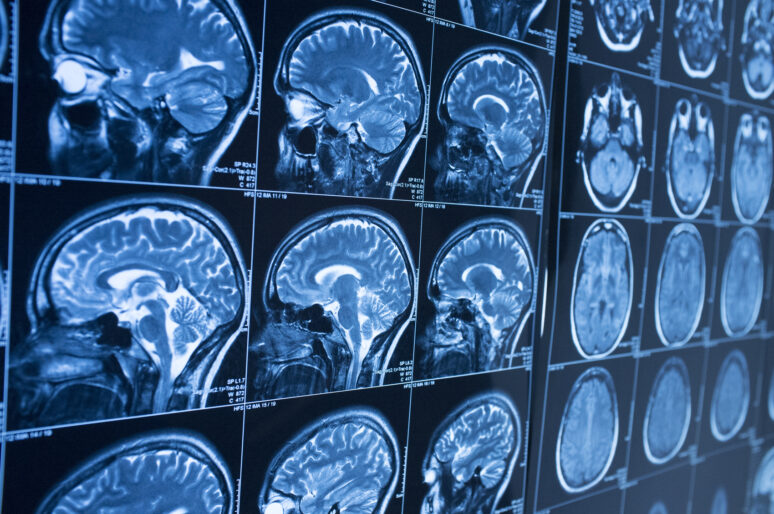

It absolutely could be linked to your brain injury. Specific parts of the brain control very different functions. One part helps keep your emotions in check. Yes, this control is a skill you learned, but it’s also a way that your brain developed.

The damage you suffered in the accident may never fully heal. If that area of your brain does not return to normal or find new neural pathways to use, you could deal with irritability and angry outbursts for the rest of your life.